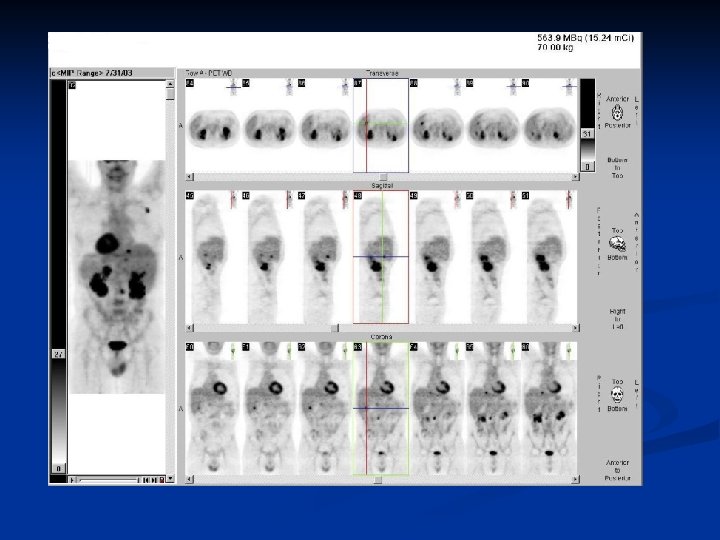

CAS CLINIQUES

Cancer pulmonaire n n n Homme 48 ans Carcinome épidermoide LSD traité par radiothérapie + chirurgie Image douteuse au niveau hépatique et rénale